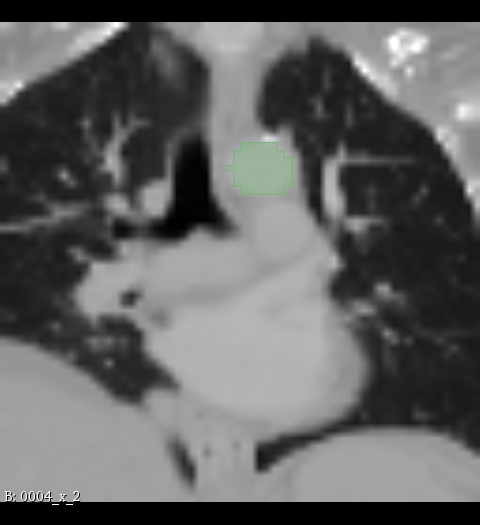

Figure 2: Illustration of the data from the TotalSegmentor data set [32] used in the experiments. The first row shows the axial, coronal and sagittal views passing the center of mass of the kidney in one of the data points. The second row shows the axial, coronal and sagittal views passing the center of mass of the aorta in one of the data points. The third row shows the axial, coronal and sagittal views passing the center of mass of the esophagus in one of the data points.

The experiments are conducted with respect to the TotalSegmentor data set [32]. This data set contains 1204 CT images with 104 anatomical structures (27 organs, 59 bones, 10 muscles, 8 vessels). To illustrate the effect noise may have on organs with different shape, three different organs are chosen. This includes the right kidney which in general is pretty spherical, the aorta which is tubular and relatively thick and the esophagus which is tubular and relatively thin. For each of the organs, 400 cases is selected and split into 5 folds of 80 cases. Finally, the images are sub-sample to half resolution and patches of 643superscript64364^{3} voxels centered in each of the structures are extracted.